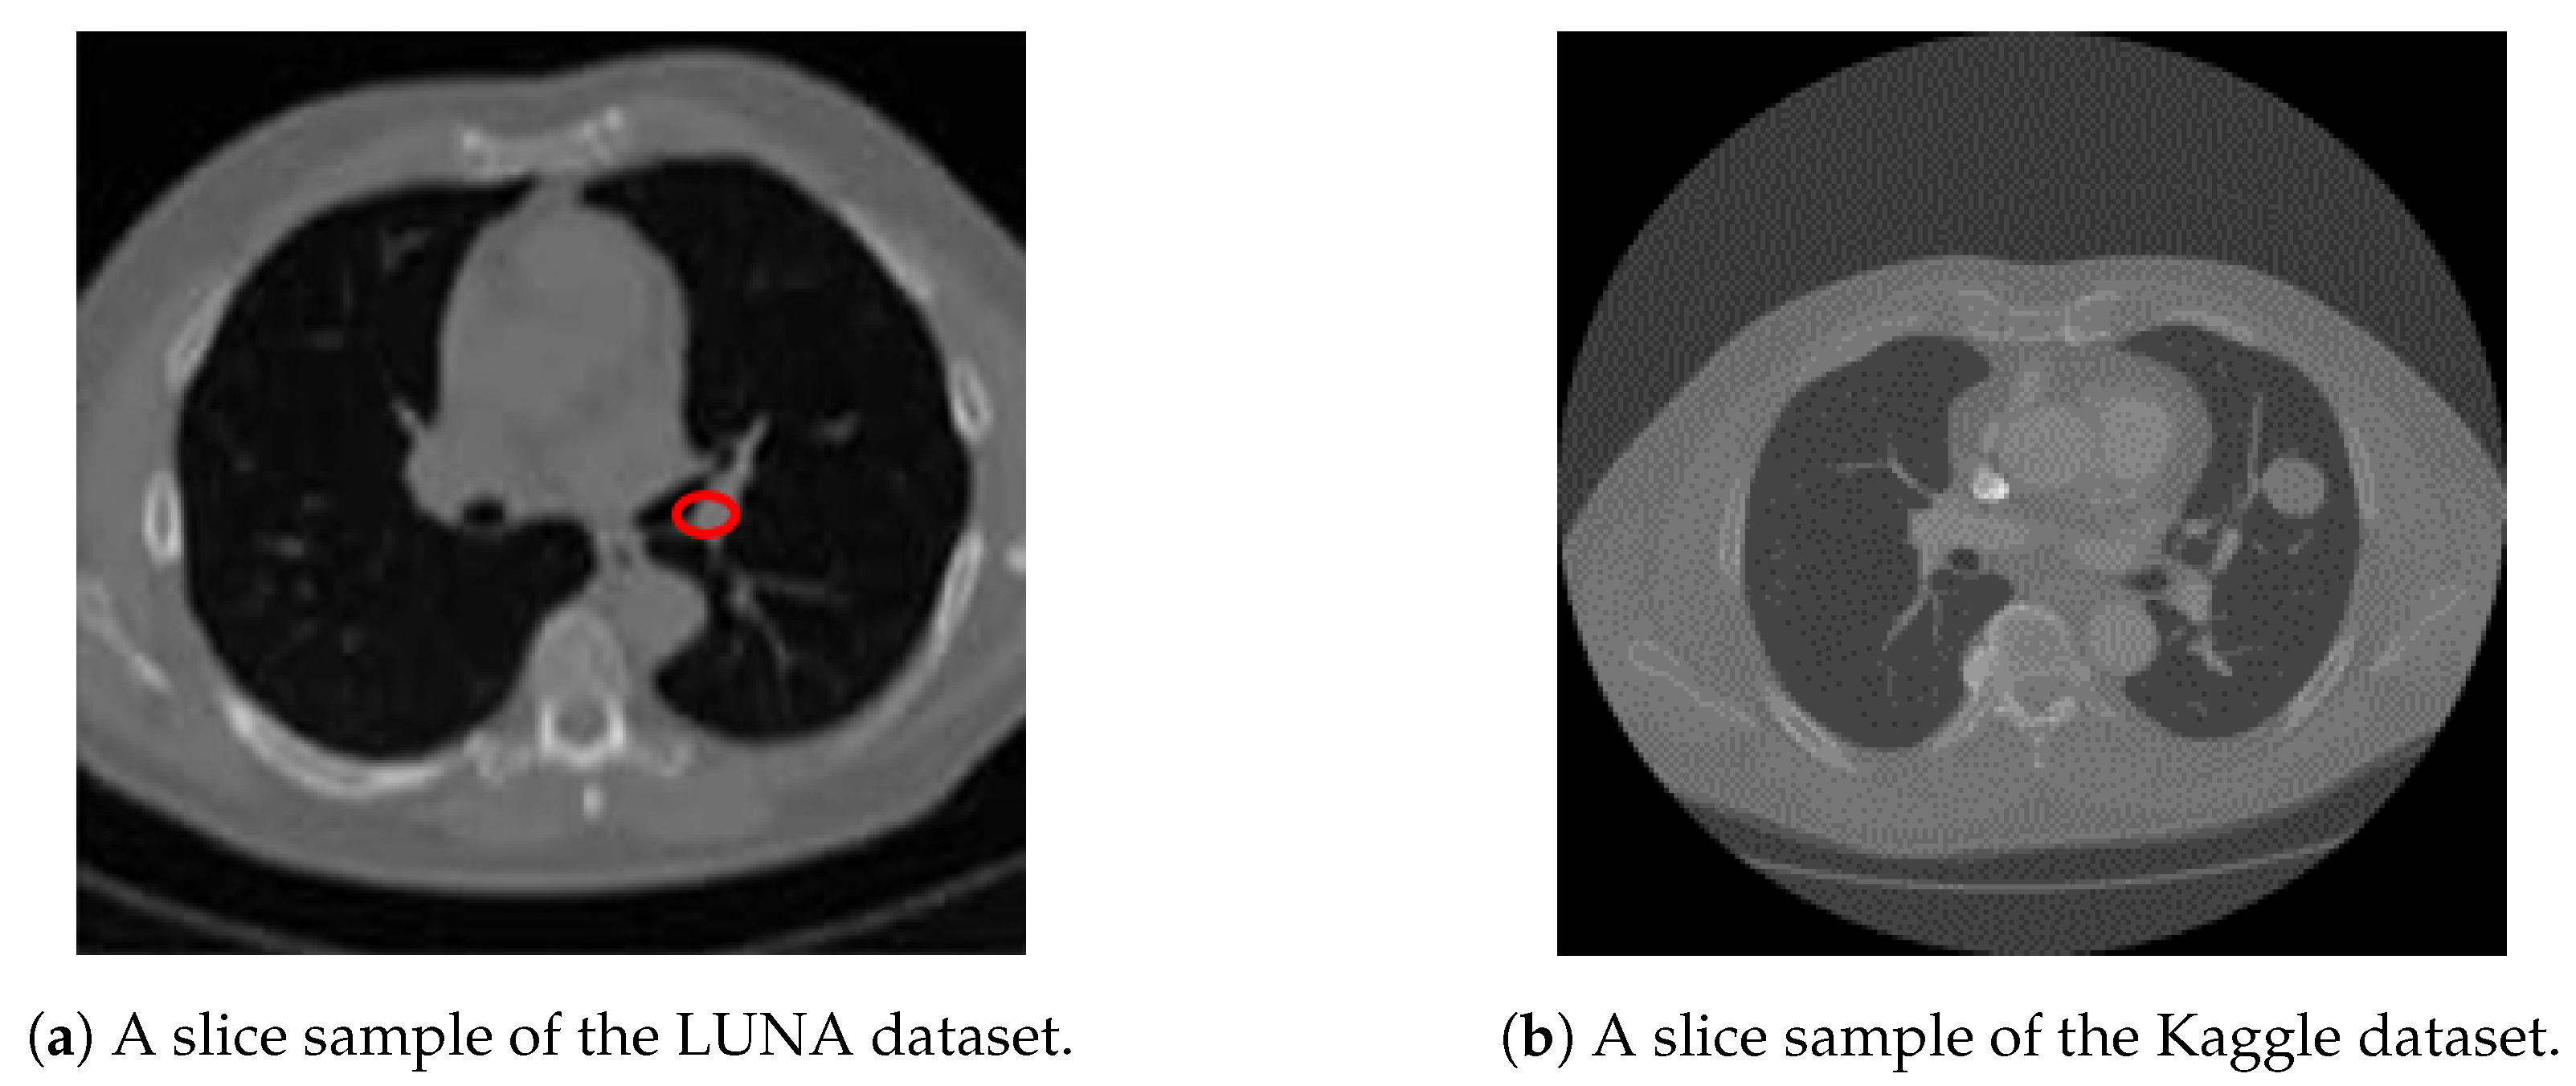

We utilize both datasets to train our system. A sample slice difference from one patient for both datasets is shown in Figure 3.

Figure 3. A sample slice from both Kaggle and LUNA datasets, showing a cross section of a patient chest cavity. Figure 3a shows a LUNA slice with an annotated nodule. Figure 3b shows that no annotations are given about nodule positions or sizes for Kaggle dataset.